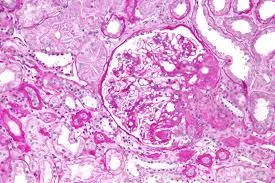

DRC “indeterminada” raramente é falta de diagnóstico — quase sempre é falta de método. Tempo de evolução, urina bem avaliada, USG renal e história clínica dirigida mudam conduta e evitam erros comuns na prática nefrológica.